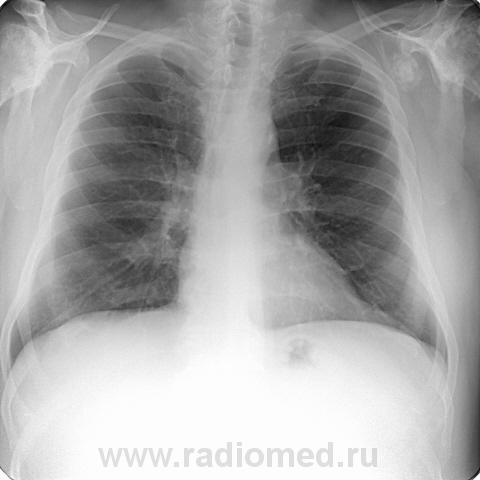

Пациент 60 лет, при прохождении проверочной флюорографии  обнаружены изменения со сторны плечевых суставов.Водитель троллейбуса.Страдает избыточной массой тела, люмбальгией, артороз коленных суставов.Непосредственно жалобы на плечевые суставы в медицинских документах не отражены. Какое будет мнение у коллег?

Пациент жалоб со сторны плечевых суставов не предъяляет и не помнит что бы когда- то что то беспокоило.Данных за сирингомиелию нет.

Александр, конечно надо доснять плечевые суставы... Из того, что есть: видимые отделы плечевых костей выглядят довольно симметрично, хотя слева и похуже, думаю - артроз. Весьма настораживает левая лопатка на предмет хондросаркомы

Уважаемый Александр, приходиться признать, что на цифровой рентгенограмме легких изменения плечевых суставов видны лучше, чем на "обрезаных" и недоэкспонированых снимках суставов. По имеющимся данным могу только сказать, что деф. артроз с кистовидной перестройкой структуры есть. Под хрящевой опухолью (возможно - хондросаркома) левой лопатки я имела в виду тень, отмеченую красными стрелками, которая в поле снимка не вошла. Моя вина - в силу специфики работы такие узкоформатные снимки давно были вредными, т.к. очень часто патология остается за пределами снимка. Остается рекомендовать рентгенография левой лопатки в прямой передне-задней и косой проекциях, а лучше - КТ...